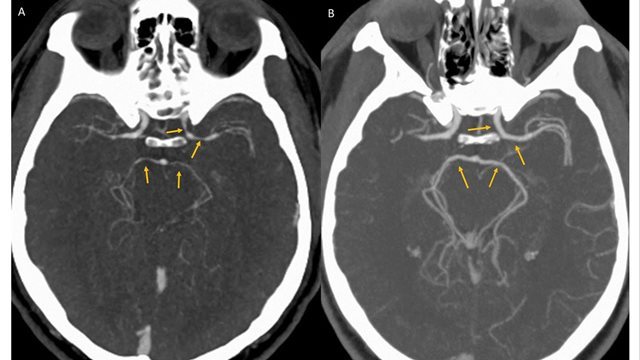

病院で検査した結果、脳出血や脳梗塞は起きていないことが判明。しかしCT血管造影を使って脳内の血管を調べたところ、左側の内頸(ないけい)動脈など脳につながる4本の血管に大きな狭窄(きょうさく)が見つかり、トウガラシが原因と思われる可逆性脳血管攣縮(れんしゅく)症候群(RCVS)と診断された。

男性は治療を受けて快方へ向かい、数日後に退院した。5週間後の検査では、血管狭窄の症状は解消されていたという。